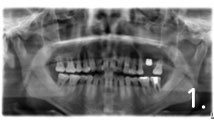

Before the surgery. There is not enough bone at back site to place implants

Implant placement and sinus bone graft were performed simultaneously on right side. Only sinus bone graft was performed on left side due to the lack of the residual bone to place implant simultaneously